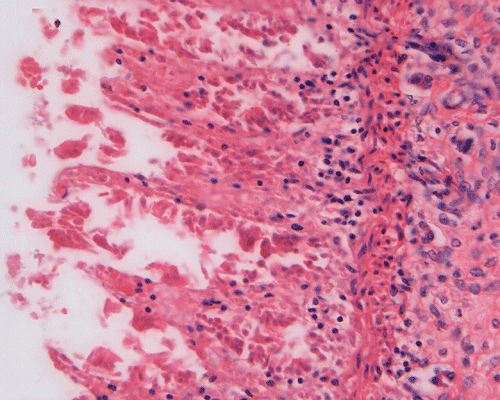

Discussion of the pathology is limited to the alimentary canal. On autopsy, the intestinal loops are largely dilated with gas accumulation. On closer examination, many small, subserosal bubbles can be seen (arrows in Panel A). The intestinal wall is also thinned out as a result of the dilatation by gas (Panel B). In the less affected areas, the intestinal  wall is not thinned out and the mucosa can still be recognized as largely intact (with autolytic changes) (Panel C and E). In the thinned out areas, the mucosa appear pink and necrotic (Panel D, F and G). The subserosal bubbles appear to be empty vesicles filled with air and they are found most frequently in the most necrotic region. In general, these features indicate widespread infarction with gas production (Panel H and I).

Coagulative and hemorrhagic necrosis is the key pathologic feature of NEC.  Necrosis is limited to the mucosa in the early stages but at least focally transmural in specimens removed from surgical resection or at autopsy.  In 10% of cases, focal necrotic pseudomembrane formation is seen.

A mixed acute and chronic inflammatory infiltrate is commonly found, limited to the mucosa in some foci but transmural in others.  Inflammation and necrosis often occur together in a given segment, but in some instances, one or the other may predominate.

Pneumatosis intestinalis, usually limited to the submucosa, is seen in 50% of surgical specimens with NEC.  The gas bubbles have been shown to contain hydrogen, a product of bacterial fermentation.  More than 50% of patients who undergo laparotomy show focal reparative epithelial changes and other evidence of healing, such as the formation of granulation tissue and crypt distortion.  Villous atrophy may also be observed.  Such reparative changes suggest that NEC evolves gradually before a catastrophic event, such as perforation, brings it to clinical attention.